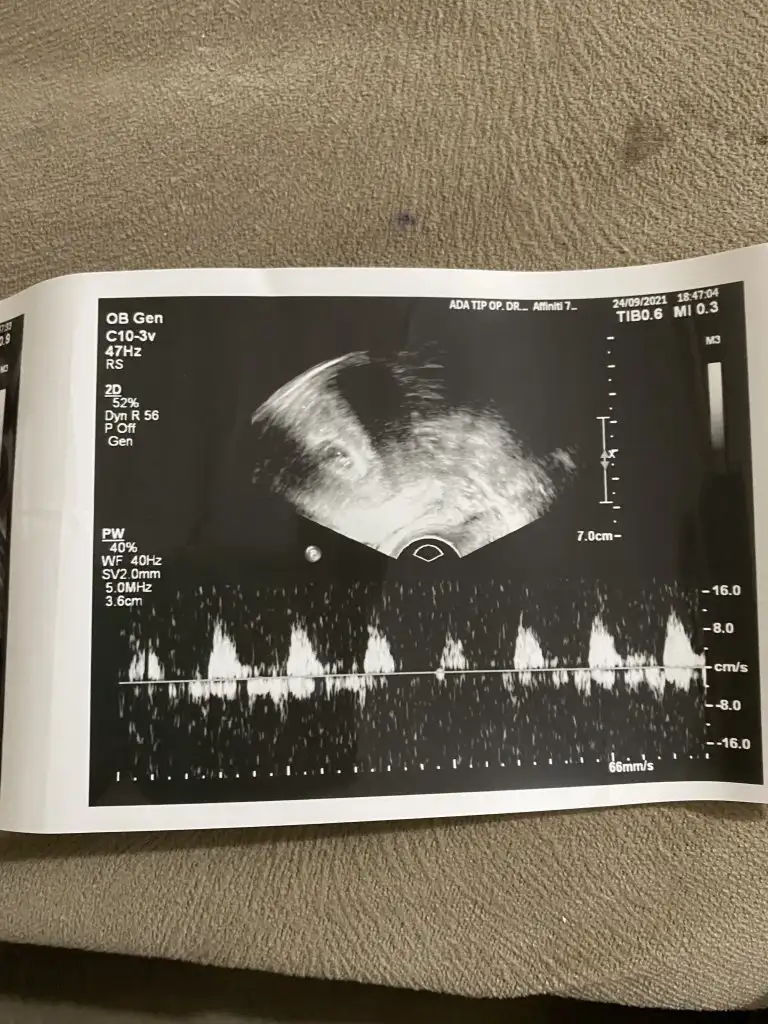

Erkek gibi sanki Emin olmadım diğerinide paylaşınKızlar merhaba. Bizde 12+2 deyiz. Sürekli hareket ettiği için en net görüntüsü bu oldu. Yorum yapabilir misiniz. Teşekkür ederim![]()

Bir gün önceki de bu şekilde. Uyuyordu sanırımErkek gibi sanki Emin olmadım diğerinide paylaşın